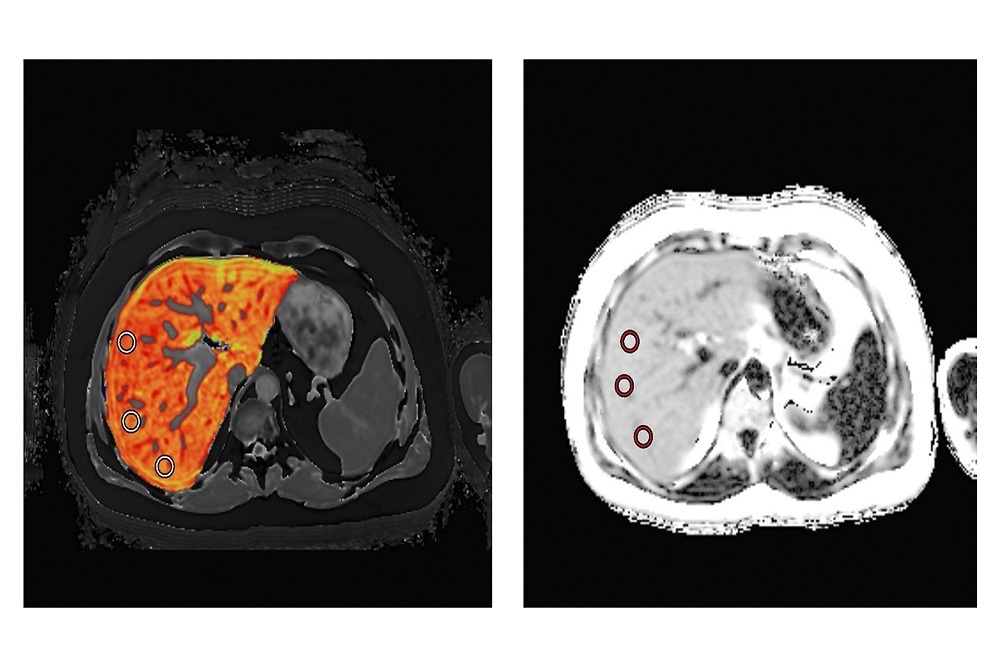

LiverMultiScan images of a liver with high cT1 values and high PDFF

These funds have been awarded under the Drug Development Tool Research Grant (U01). The study will qualify the imaging markers cT1 and PDFF as drug development tools in non-alcoholic steatohepatitis (NASH); initially as diagnostic screening biomarkers to identify patients for inclusion in NASH clinical trials, then as pharmacodynamic efficacy biomarkers to detect clinically meaningful change, with the ultimate objective being approval as non-invasive surrogate endpoints. LiverMultiScan will help identify patients for NASH clinical trials.